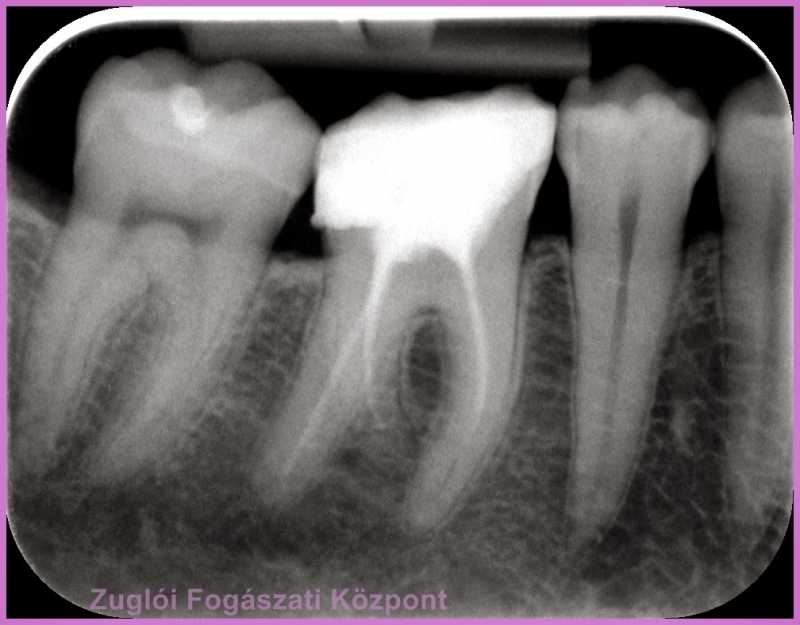

Kolléganőnk kicserélte a gyökértömést, ezen a röntgenfelvételen a kezelés utáni állapot látszik.

gyökértömés csere utáni állapot